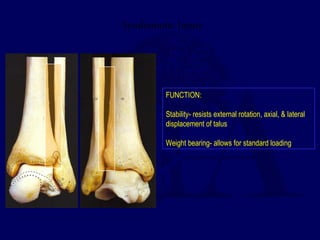

Syndesmotic Injury

FUNCTION:

Stability- resists external rotation, axial, & lateral

displacement of talus

Weight bearing- allows for standard loading